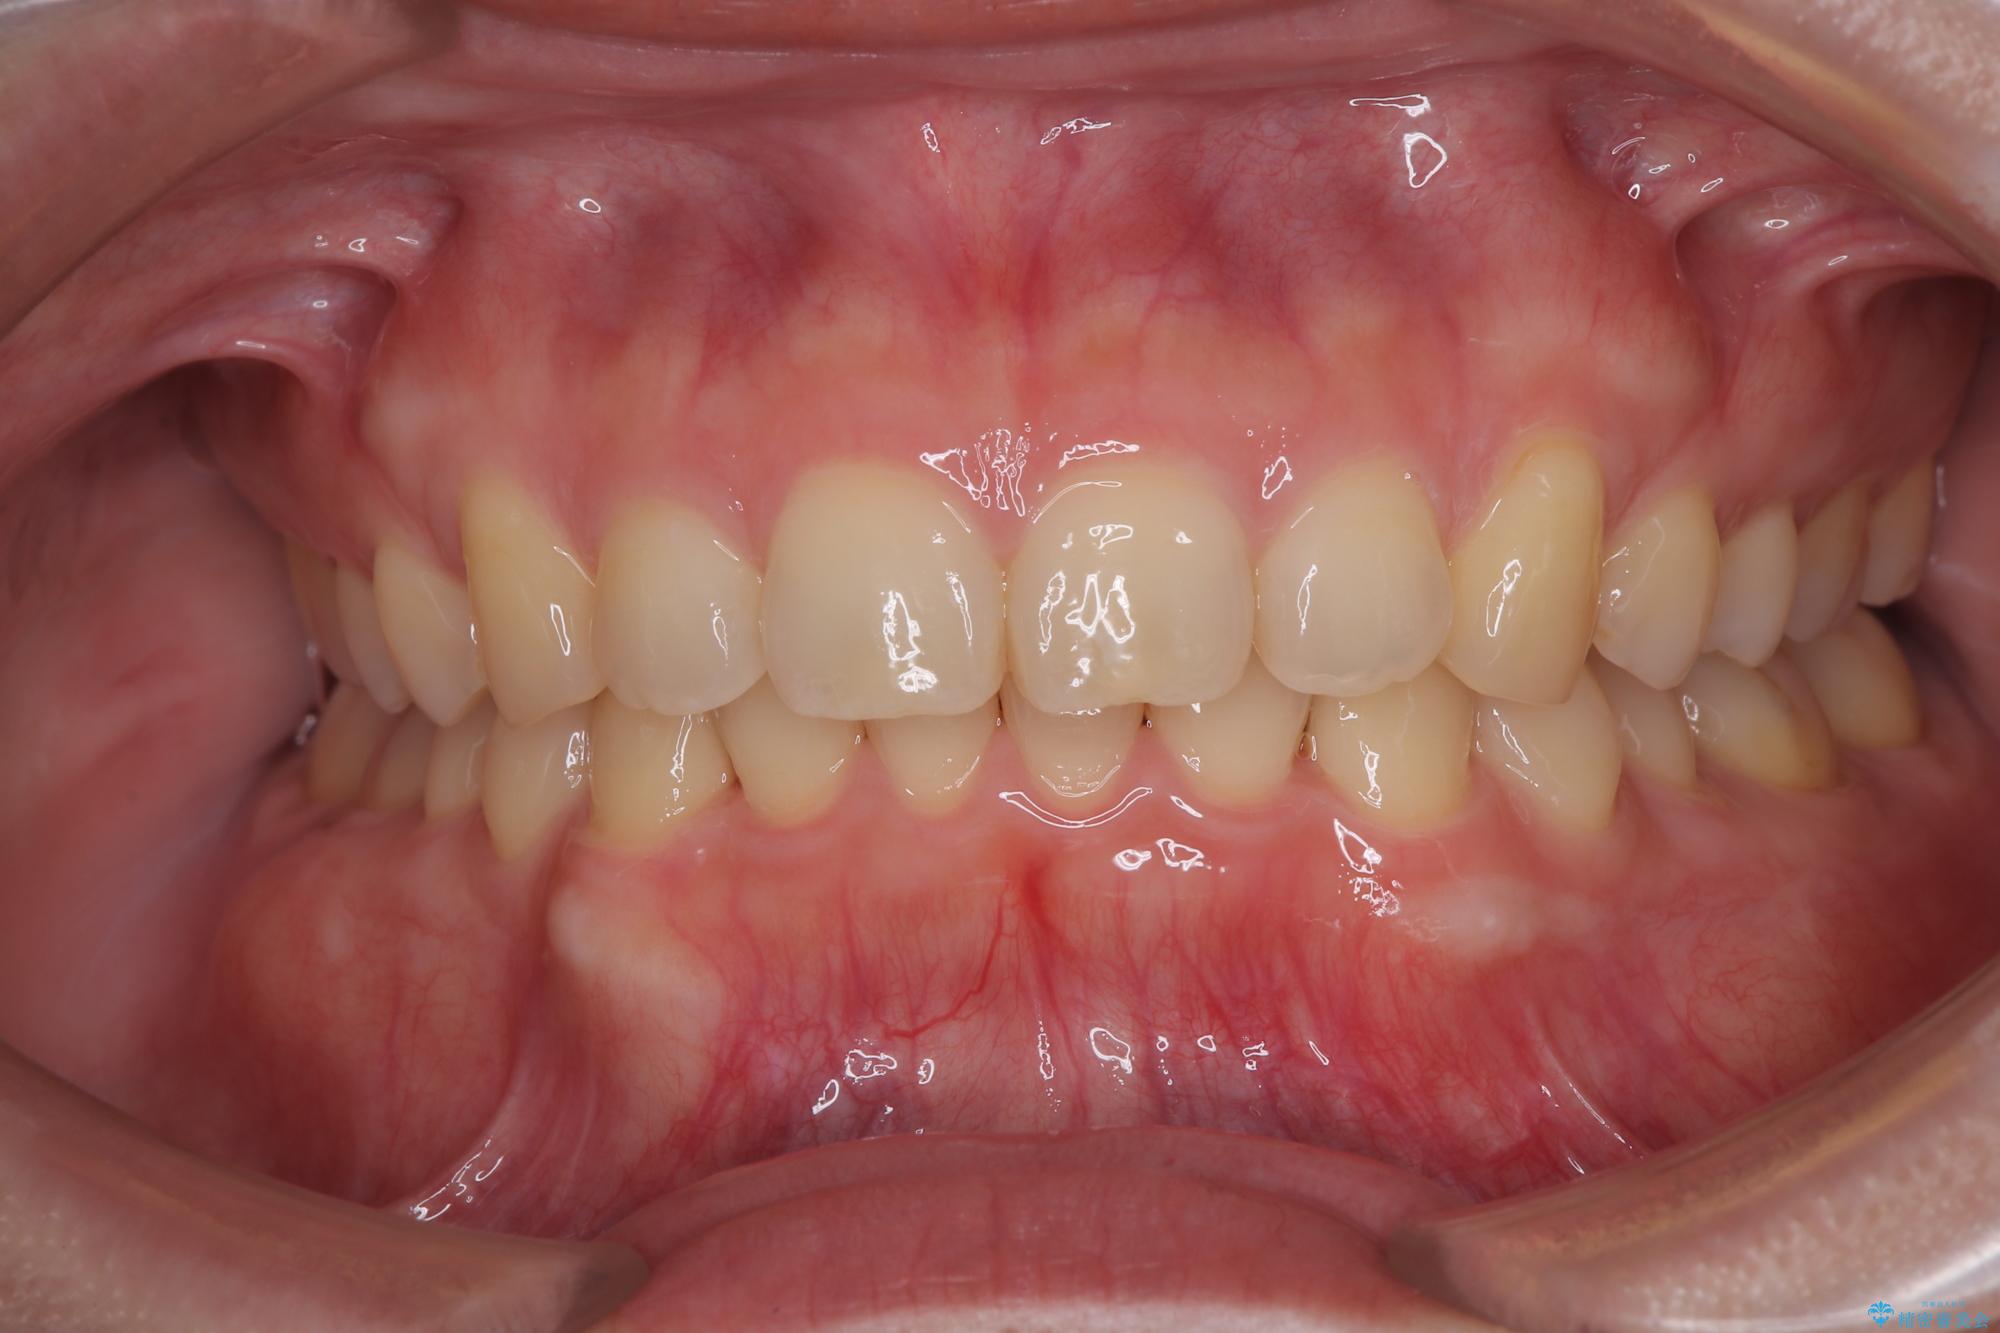

隠れた前歯が気になる ディープバイトのワイヤー矯正治療

下顎臼歯を起き上がらせるためにユーティリティーアーチを使用し、一気に深い咬み合わせを改善することができました。